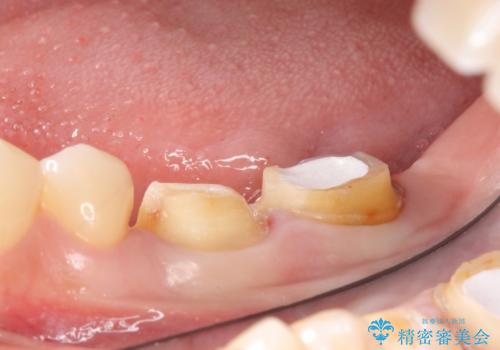

検査の結果左下7は失活(歯の神経が死んでいること)しておりX線上で根尖病変を認めたため、根管治療を行いました。

歯周外科手術終了後、歯茎の回復を待ち左下6、7ともにオールセラミッククラウン(スタンダード)による補綴を行いました。